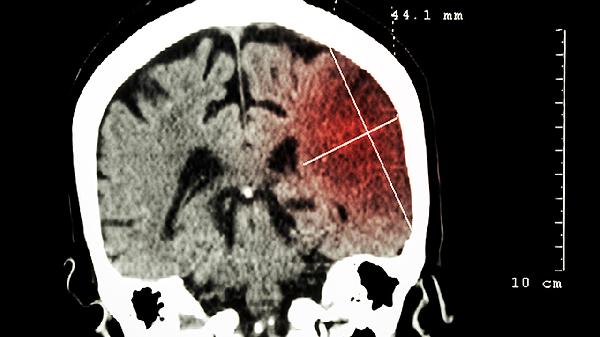

突发的炸裂样头痛伴随喷射性呕吐,需排查蛛网膜下腔出血或脑出血。常见于高血压患者血管破裂,可能伴随颈项强直和畏光症状。CT能快速显示出血部位,必要时需联合腰椎穿刺检查。急性期可使用尼莫地平片预防血管痉挛,配合氨甲环酸注射液控制出血。

突发半身无力或感觉异常提示脑卒中可能,CT可鉴别脑梗塞与脑出血。发病3小时内可见缺血半暗带,超过24小时能显示梗死灶。常伴随言语含糊和面瘫,需紧急评估后使用阿替普酶注射液溶栓。腔隙性梗死患者可选用阿司匹林肠溶片联合氯吡格雷片抗血小板治疗。